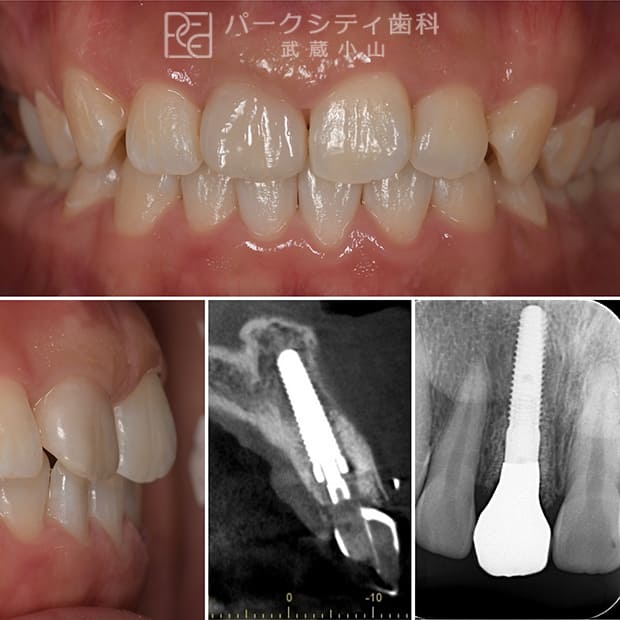

ルートメンブレンテクニックを併用した前歯部抜歯即時埋入の症例

ルートメンブレンテクニックとは歯根を一部温存することにより、顎堤の吸収を抑止することができるため審美的によい結果が得られます。また、今回大きな切開や移植などしていないため腫れや痛みも少なく、治療期間も短くてすみます。